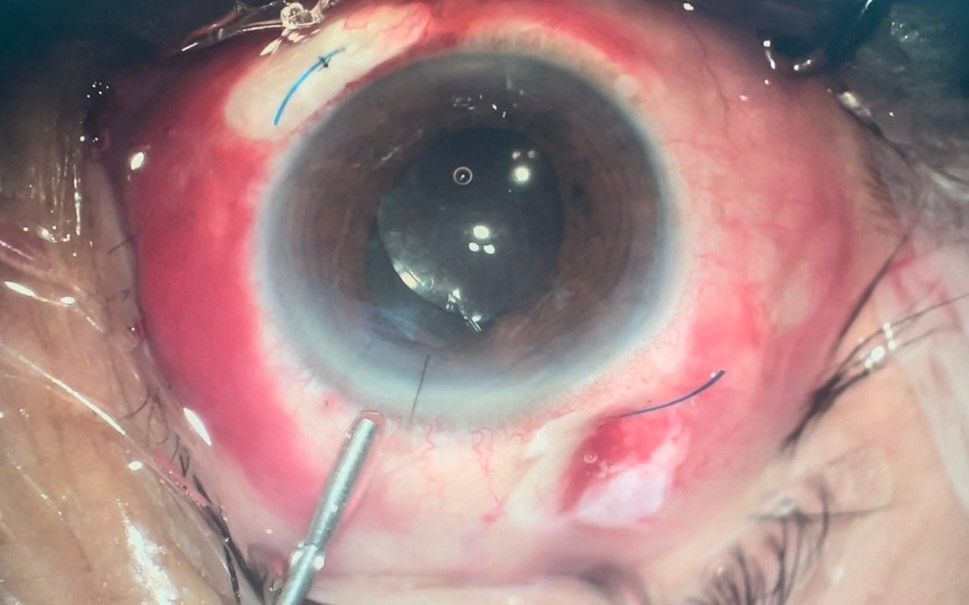

+ Phẫu thuật lấy thủy tinh thể bị lệch và cố định thủy tinh thể nhân tạo

Nếu TTT sa vào buồng dịch kính: Khi phát hiện các biến chứng kèm theo như: Tổn thương võng mạc, viêm màng bồ đào, bong võng mạc.. thì chỉ định phẫu thuật.  |  |  |

| TTT bị lệch (không hoàn toàn) | Phẫu thuật cố định IOL | Sau phẫu thuật |